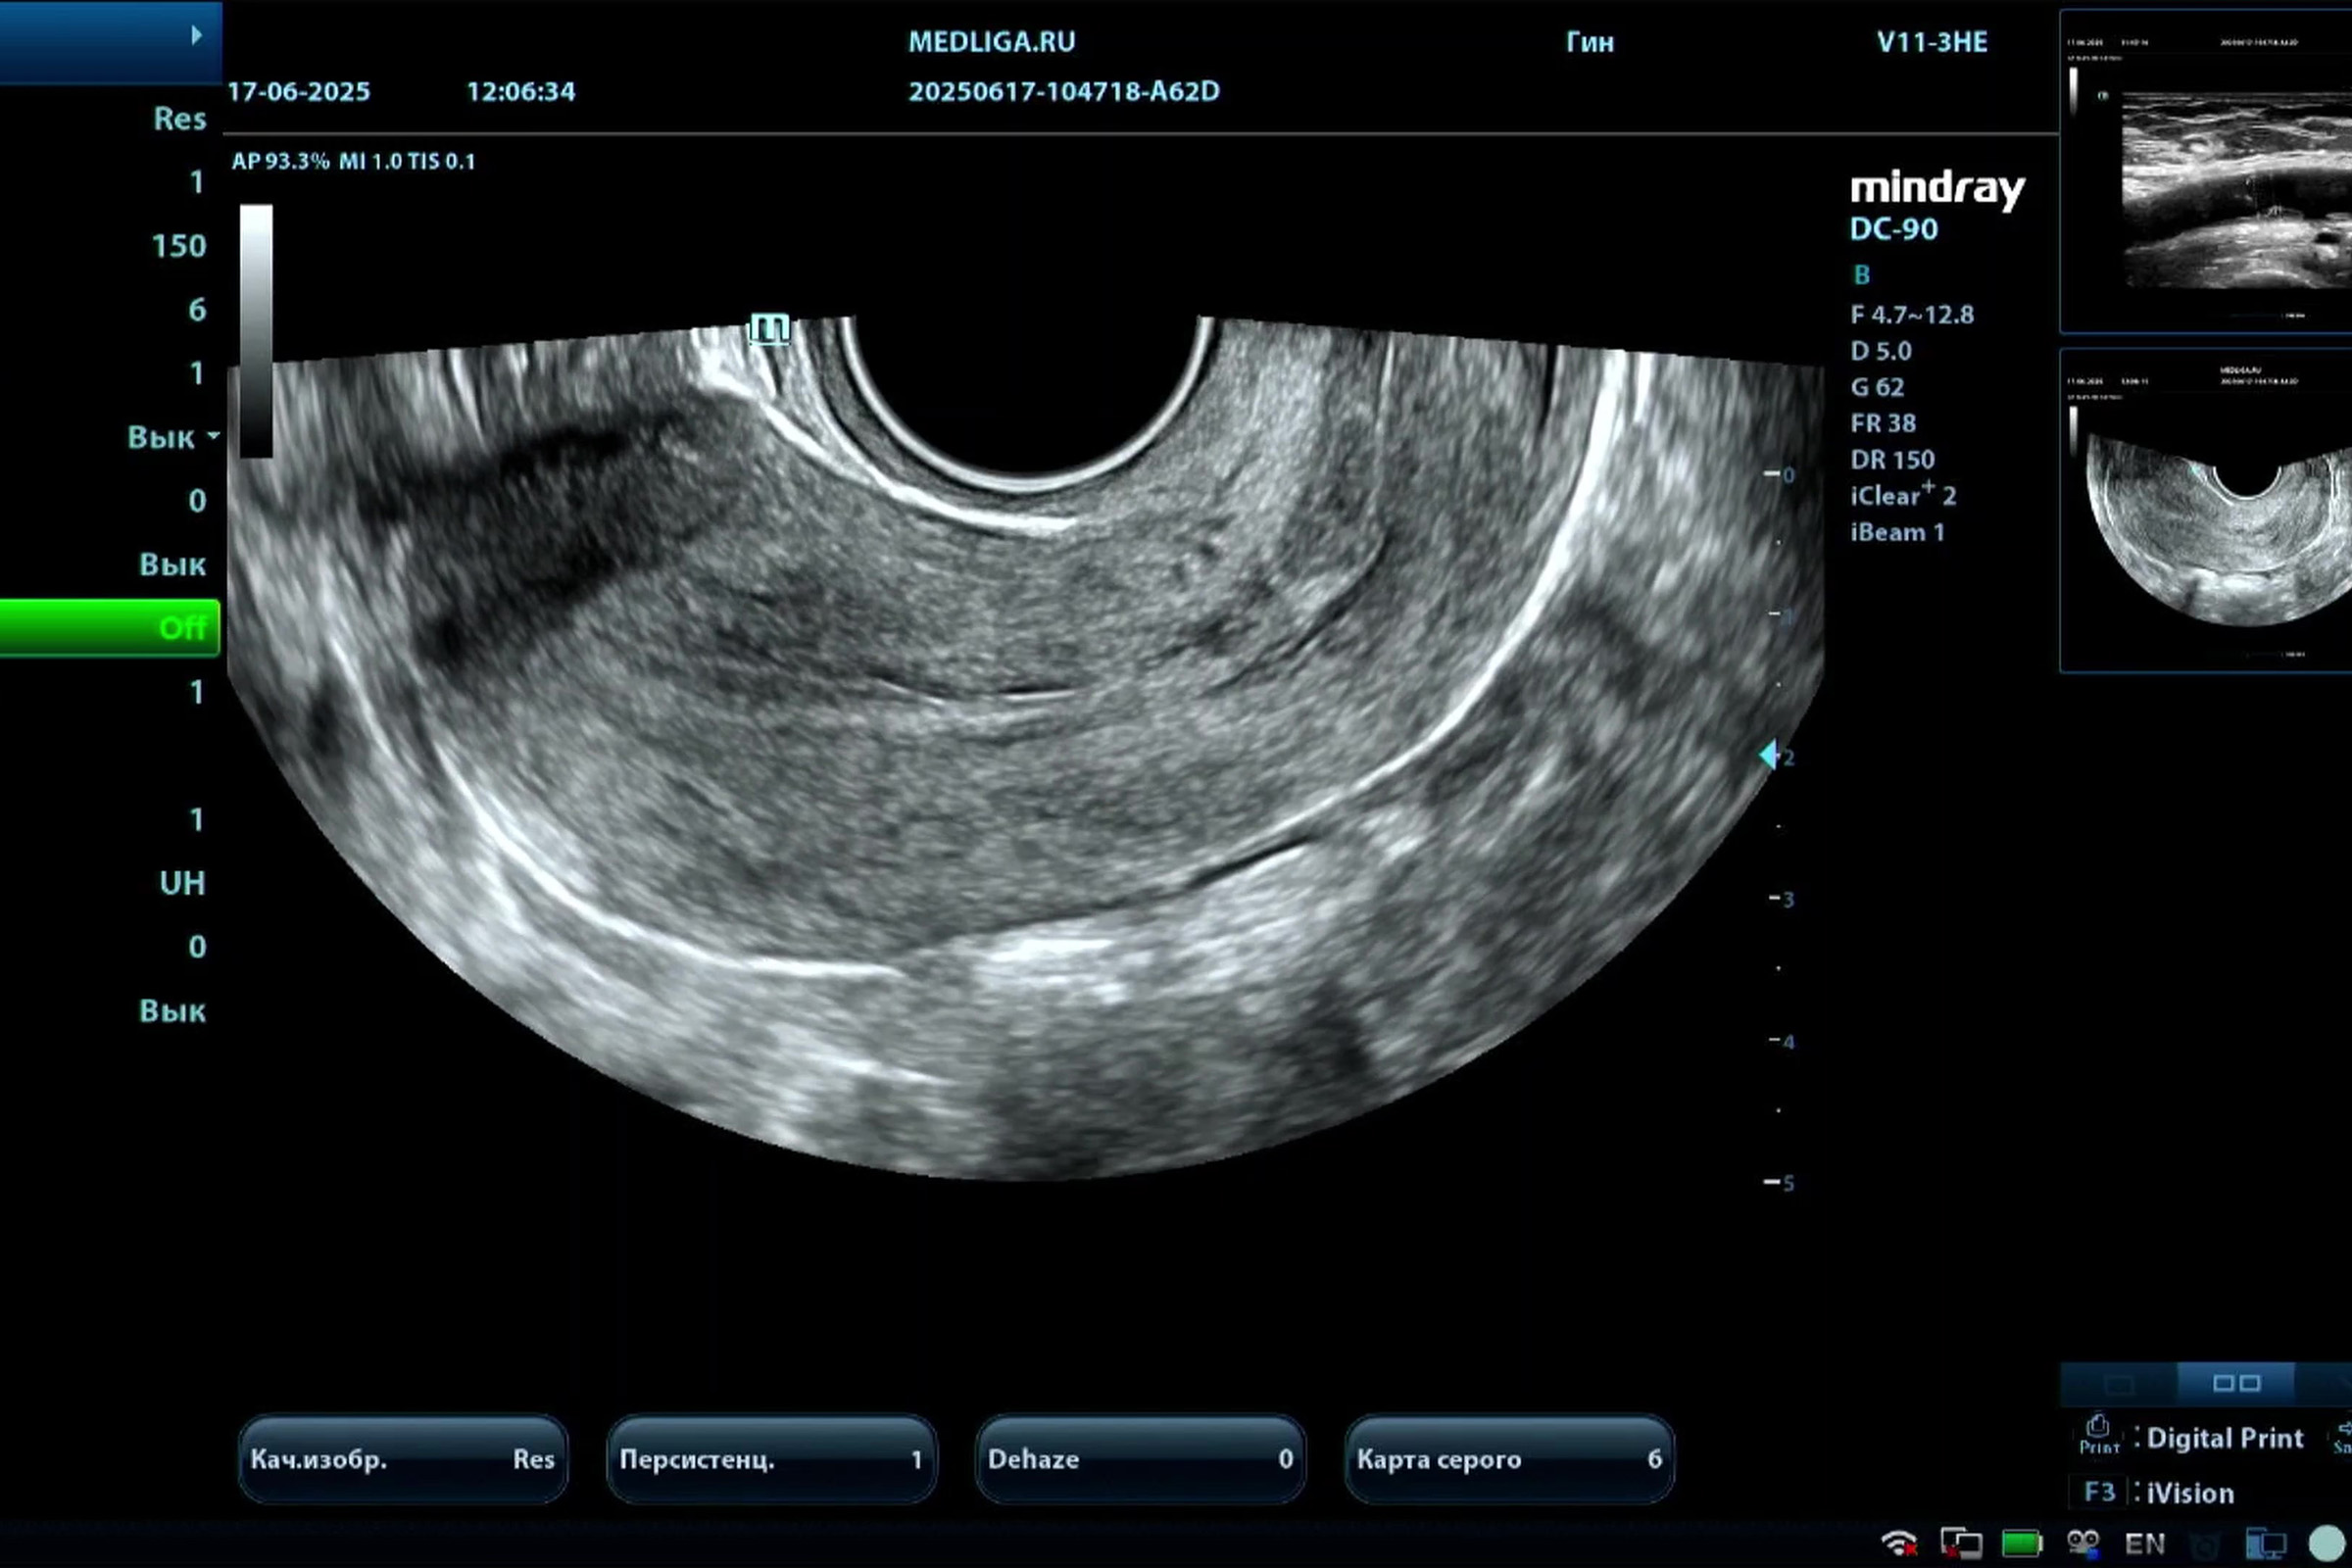

Медицинское оборудование для ультразвуковой диагностики